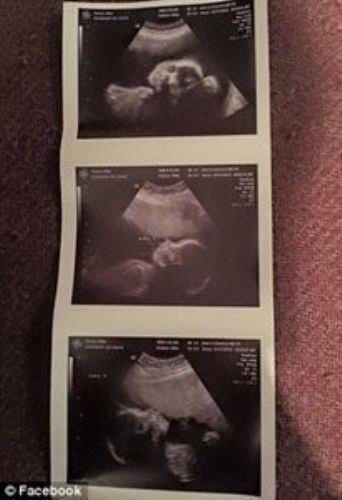

Geçtiğimiz günlerde Teksas’ta nadir görülen bir üçüz doğum gerçekleşti.

Silvia Hernandez ve Raul Torres çifti; Catalina, Ximena ve Scarlett adını verdikleri bebeklerini beklediklerinden birkaç gün önce kucaklarına aldılar.

Üçüzlerden ikisinin yapışık olduğunu öğrendiklerinde, hamilelik süreci onlar için daha da zorlaştı.

Bu da doğal bir gebelikte, yapışık ikizlerin olduğu üçüz bir doğumun 50 milyonda bir olduğu anlamına geliyor.